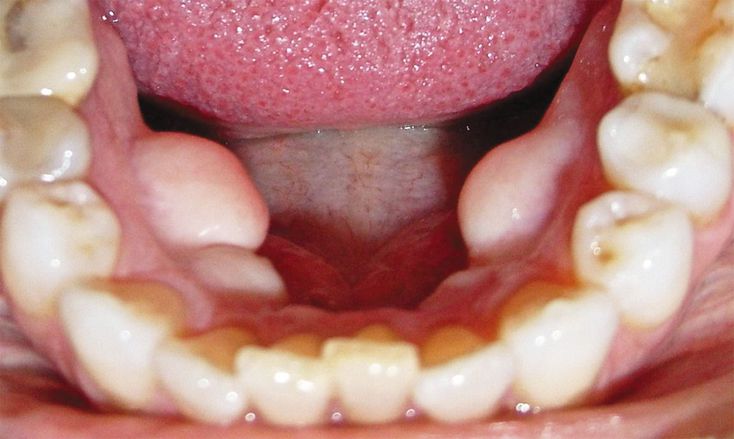

A 62-year-old woman presented for a routine dental examination. During the examination, she was asked about the increased tissue on the lingual surface of her lower jaw. The patient reported that the mass had been growing slowly for years and that several family members had similar growths. She reported no pain, pruritus, or other symptoms. On examination, four hard, sessile nodules were noted on the lingual surface, with normal overlying mucosa. No notable abnormalities were identified on panoramic radiographs. Exostoses are localized, benign bony protrusions. The most common oral exostoses are torus palatinus and torus mandibularis, which do not have cartilage involvement, owing to their anatomical location. There are many reasons for the development of exostoses, including genetic and environmental causes. They are generally asymptomatic. Removal of oral exostoses may be indicated before prosthetic rehabilitation or if complications from chronic trauma develop. Since this patient was asymptomatic, no intervention was required.